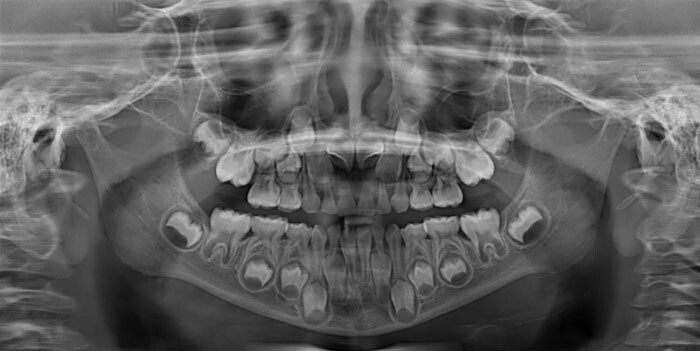

«У меня клейдокраниальный дизостоз, или, если проще, у меня в челюсти много лишних „запасных“ зубов»